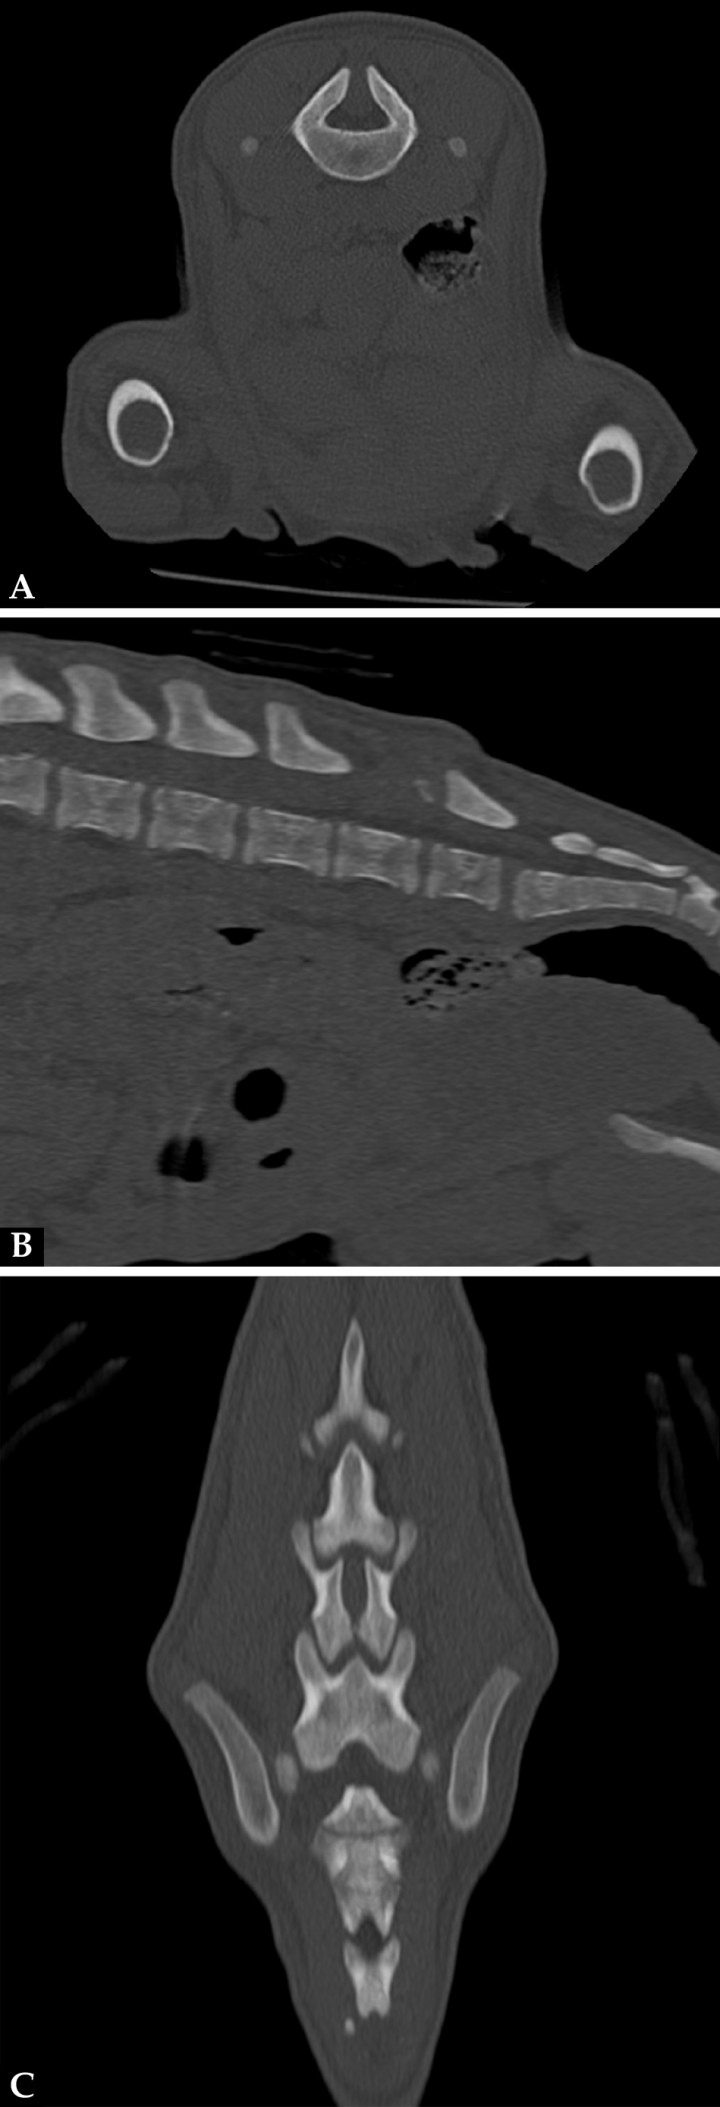

La mielografía podría ayudarnos a valorar el espacio subaracnoideo si sospechamos de un MC/MMC, aunque las técnicas de imagen avanzada, tomografía computarizada (TC) y resonancia magnética (RM) son las pruebas recomendadas si se sospecha de un defecto del tubo neural (DTN). Se realizó un estudio TC (General Electric Brivo CT385 Series de 16 cortes, Hangwei Medical Systems Co Ltd, Beijing, China, 16 cortes) sin y con contraste intravenoso, en el que se observó hipoplasia de la apófisis espinosa de L6 sin fusión de las láminas dorsales dejando un espacio abierto que comunicaba el canal vertebral y el tejido blando lumbar caudodorsal a L6 (Fig. 3). En las imágenes obtenidas en ventana de tejidos blandos tras administración de contraste se apreció el paso por el defecto espinal de tejido del canal vertebral con atenuación tejido blando y realce periférico, hasta el tejido blando dorsal a L6-7 (Fig. 4).

Imágenes de TC en ventana de hueso. (A) Plano transversal. (B) Reconstrucción en plano sagital. (C) Reconstrucción en plano dorsal. Hipoplasia de la apófisis espinosa de L6 sin fusión de las láminas dorsales dejando un espacio abierto que comunica el canal vertebral y el tejido blando lumbar caudodorsal a L6